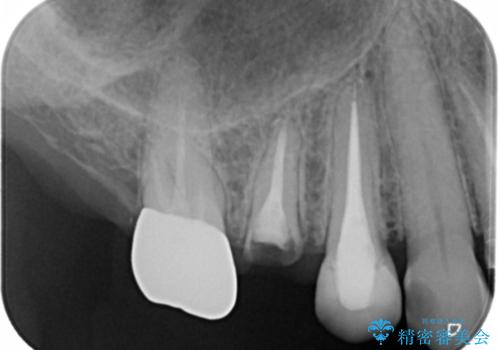

- 右上小臼歯の破折を理由に来院された患者様です。

残根状態で保存不可能と判断し、抜歯した上で補綴することを提案しました。

インプラント治療を希望されたので治療の期間・回数の少ない抜歯即時埋入インプラントでの治療を計画しました。